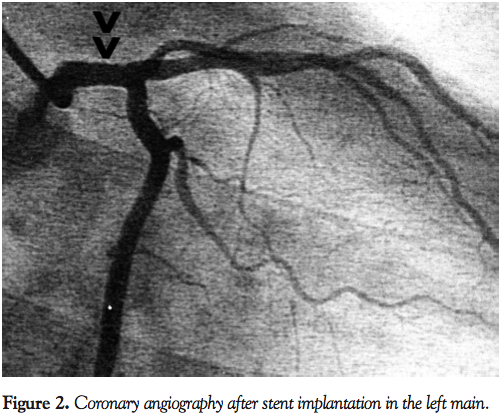

All 34 patients included in the study and treated percutaneously received aspirin (100 mg) and clopidogrel (300 mg) before the procedure and 50 to 80 IU/kg intra-arterial bolus of unfractionated heparin at the start of PCI. The ostium of the LM was treated in 7 patients (21%), the body of the LM in 2 patients (6%), and the distal part of the LM in 25 patients (74%). Direct coronary stenting with implantation of only one stent covering the LM and proximal part of the left anterior descending artery (if needed) was the primary technique used in this study.6,7 Stents with a nominal diameter of 3.5 to 4.5 mm were used (Figures 1 and 2). High-pressure balloon postdilation or kissing-balloon postdilation were used at the operator’s discretion. The following drug-eluting and bare-metal stents were used: Xience Prime Coronary Stent System (Abbott Vascular), BioMatrix (Biosensors International), FlexMaster F1 coronary stent (Abbott Vascular), and Coroflex Blue (B. Braun). Three bare-metal stents and 31 drug-eluting stents were used. After PCI, aspirin, statins, and other optimal medical treatments were prescribed to all patients. Clopidogrel 75 mg/day was prescribed for 1 month after the implantation of bare-metal stents and for 6 to 12 months after the implantation of drug-eluting stents.